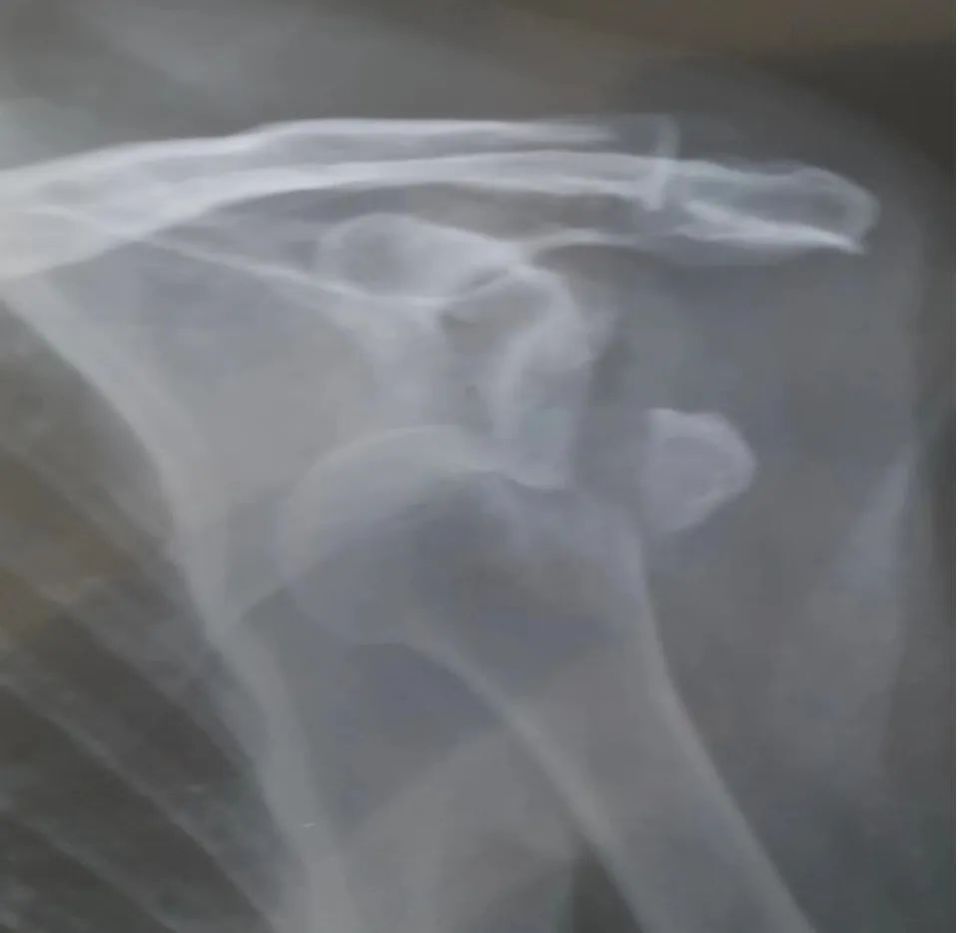

做完手术的第二天上午,医生通知我去术后拍片。因手无法抬到所要求的角度,费了不少时间,后来还是把女儿叫进了拍片室,在她的协助下我才勉强完成。

术后复查X光丨作者供图

手术后就只需每天止疼消炎,还要在肚皮上注射低分子肝素钠防血栓。术后感觉一切良好,就是医院的环境我睡不好觉,多次央求管床医生后,我终于出院了。在换下病号服之前,特意对镜自拍一张,以示留念。